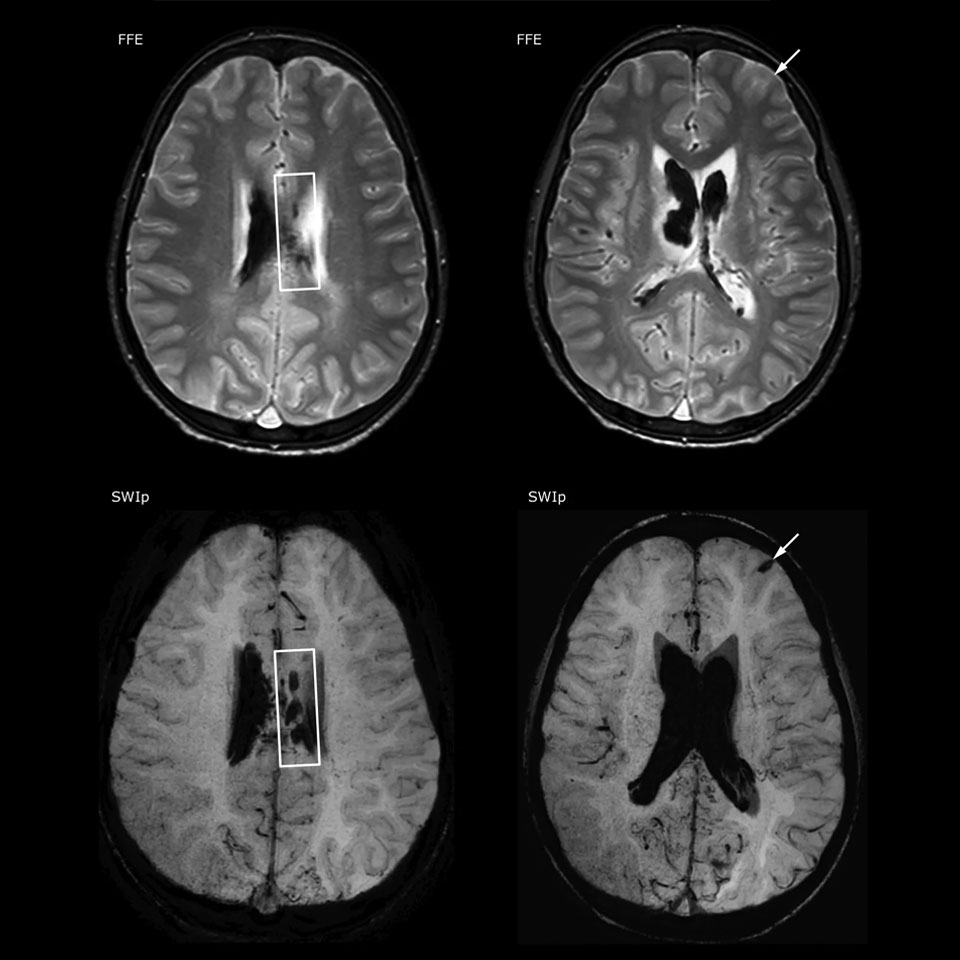

Der Nutzen suszeptibilitätsgewichteter Bildgebung bei der Darstellung von Gehirnverletzungen ist gut dokumentiert. Das Multi-Echo-SWIp-Verfahren von Philips liefert eine schnelle, suszeptibilitätsgewichtete Bildgebung mit verbessertem Suszeptibilitätskontrast und hoher Auflösung.

„Die pädiatrische Bildgebung stellt uns durchaus vor Herausforderungen“, sagt Dr. Miller. „Da unsere Patienten häufig sehr klein sind, benötigen wir eine Bildgebung mit hoher Auflösung. Bei Gehirnverletzungen benötigen wir schnell Informationen, damit das Klinikteam die erforderlichen Entscheidungen treffen kann. Wir sind auf eine hohe Auflösung und robuste Bildgebungskapazitäten angewiesen – Merkmale, die SWIp bereitstellt.“

„SWIp hilft uns bei der Erkennung von Blut oder Blutkomponenten, Kalzifizierung und Erkrankungen des Gefäßsystems“, führt Dr. Miller aus. „Bei Kindern mit Schädel-Hirn-Traumata werden die verletzten Bereiche hervorgehoben, und zwar besser als mit einigen der Verfahren, die wir früher angewendet haben. Diese Kinder weisen häufig Mikroverletzungen auf, die zu kleinen Blutungen oder Gewebeläsionen führen. Mit Hilfe von SWIp können wir das Ausmaß und die Art der Verletzung besser beurteilen. Die optimale Charakterisierung einer Verletzung unterstützt die diagnostische Sicherheit.“

„Ich würde anderen Benutzern die Implementierung von SWIp definitiv empfehlen. Wir fügten die SWIp-Sequenz anfangs hinzu, weil deren Einsatz in der Literatur sehr positiv bewertet wurde. Dann verglichen wir SWIp direkt mit den bei uns eingesetzten 2D-Gradientenechosequenzen. Nach einer Vielzahl von klinischen Erfahrungen, die den Nutzen belegten, entschieden wir uns, die alten Sequenzen durch SWIp zu ersetzen. Wir können damit die pathologischen Prozesse im Gehirn besser beurteilen, die bei unseren bisherigen Bildgebungssequenzen weniger offensichtlich waren“, erklärt Dr. Miller. „SWIp ist mittlerweile eine Routinesequenz für die Bildgebung bei Patienten mit Schädel-Hirn-Traumata am PCH, und sie wird episodisch auch bei Patienten eingesetzt, die intrakranielle Gefäßveränderungen aufweisen.“

„Ich glaube, dass SWIp sich aufgrund der hohen Sensitivität für venöse Blutkomponenten rasch zum Bildgebungsstandard bei Schädel-Hirn-Traumata entwickeln wird. SWIp kann auch bei der Gewinnung von Patienten helfen. So bitten unsere Neurochirurgen häufig darum, dass die Patienten mit unseren Scannern untersucht werden, die über hochempfindliche Verfahren wie SWIp verfügen. SWI-Sequenzen werden zudem immer häufiger bei anderen Gefäßveränderungen angewendet, da sie Optionen zur physiologischen Beurteilung des Gehirns bieten, die über eine standardmäßige strukturelle Bildgebung hinausgehen.“